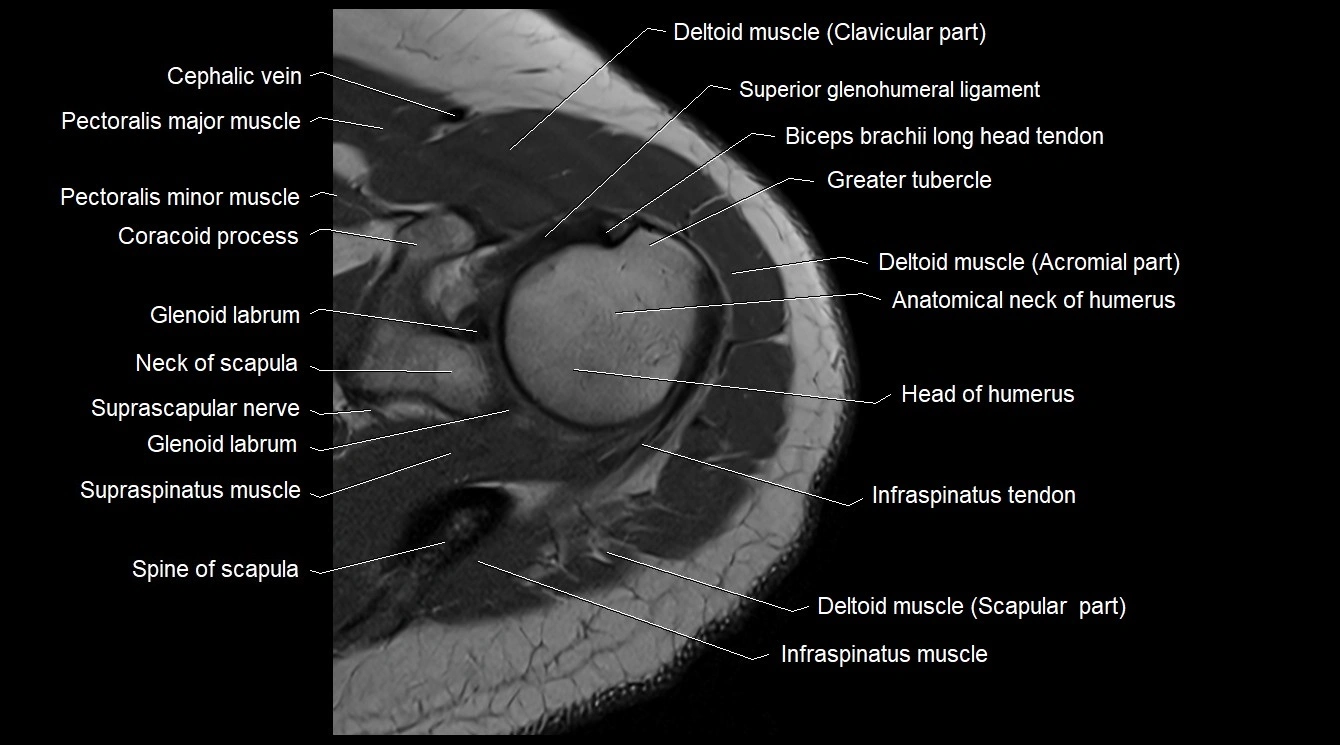

- Cephalic vein

- Clavicular part of deltoid muscle

- Glenoid labrum

- Greater tubercle of humerus

- Head of humerus

- Infraspinatus muscle

- Infraspinatus tendon

- Pectoralis major muscle

- Pectoralis minor muscle

- Spine of scapula

- Superior glenohumeral ligament